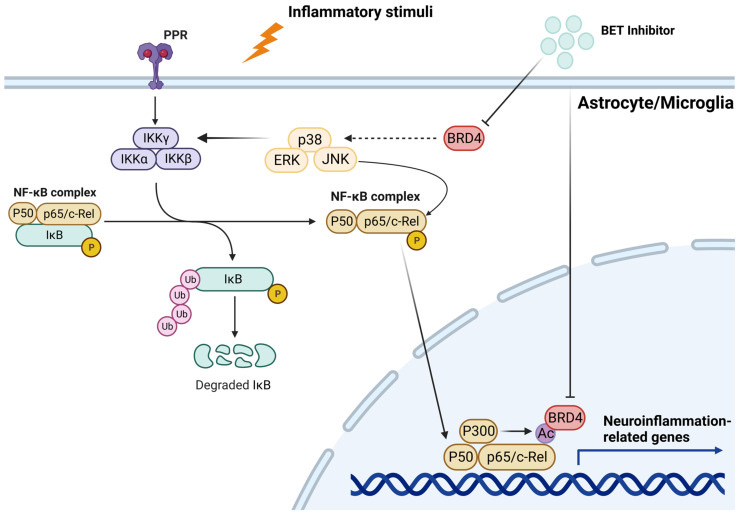

BET proteins can contribute to neuroinflammation, as per Martella et al (2023)19.

In recent years, thanks to the development of BET inhibitors, interest in this protein family has risen for its relevance in brain development and function. For example, experimental evidence has shown that BET modulation affects neuronal activity and the expression of genes involved in learning and memory. In addition, BET inhibition strongly suppresses molecular pathways related to neuroinflammation. These observations suggest that BET modulation may play a critical role in the onset and during the development of diverse neurodegenerative and neuropsychiatric disorders, such as Alzheimer’s disease, fragile X syndrome, and Rett syndrome.

In the nervous tissue, microglia are key players in the regulation of innate immune response and neuroinflammation [125,126]. Specifically, recent data demonstrate that enhanced degradation of BET proteins achieved by PROteolysis-TArgeting Chimera (PROTAC) technology blunted the LPS-induced pro-inflammatory response in the murine microglial cell line SIM-A9. In detail, treatment with dBET1 induced a significant degradation of BRD2 and BRD4, which was associated with a considerable reduction in iNOS and COX-2 levels. Furthermore, BET degradation attenuated the expression of different pro-inflammatory genes, such as Nos2, Ptgs2, Il-1β, Tnfα, Ccl2, Il-6, and Mmp9.

Recent studies employed models of permanent and transient cerebral ischemia to evaluate the effects of BET inhibition on the inflammatory response mediated by NF-kB [131,132,133,134]. In rats, transient cerebral ischemia obtained by middle cerebral artery occlusion (MCAO) resulted in a significant increase in BRD4 expression in the MCAO group compared to the control group, which was prevented by JQ1 treatment. JQ1 administration also hindered the infarct volume, reduced the number of apoptotic cells, and decreased the expression of pro-inflammatory factors (IL-1β, IL-6, IL-17, and TNF-α) in the ischemic brain. Notably, BET blockade suppressed neuroinflammation by reducing p65 levels and by increasing the cytosolic expression of the NF-kB inhibitor IkB [131]. Other reports corroborate these findings, demonstrating that NF-kB suppression by BET blockade markedly hampered the expression of pro-inflammatory mediators, leading to the reduction in pyroptosis and inflammasome activation. From a functional point of view, the molecular changes promoted by BET inhibition were associated with a partial recovery of neurological deficits [132].